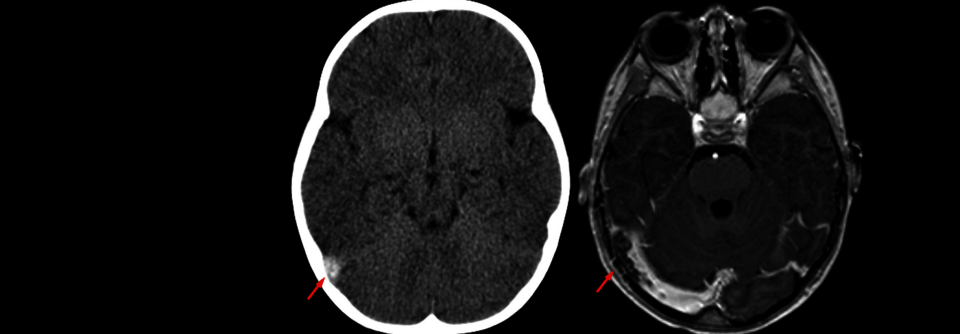

Demenzdiagnostik und -therapie

Was ist wichtig in der Hausarztpraxis?

Ist eine frühe Diagnostik bei Demenz sinnvoll? Warum ist die Bildgebung hierbei so wichtig? Welche Diagnose-Tests stehen für die Hausarztpraxis zur…

Neurologie , Geriatrie